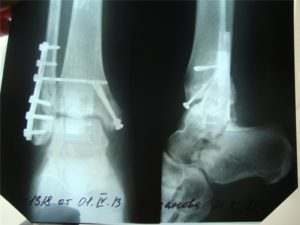

- При наличии смещения костных отломков производится ручная репозиция или оперативное вмешательство с фиксацией отломков пластинами или винтами.

После наложения гипсовой повязки проводится контрольное рентгенологическое исследование. Оно помогает определить, не произошло ли смещение костных отломков во время жесткой фиксации голени.

Через несколько дней после наложения повязки к гипсу прикрепляется стремя или каблук, которые помогают правильно перераспределять нагрузку на пораженную конечность и разгружать область перелома.